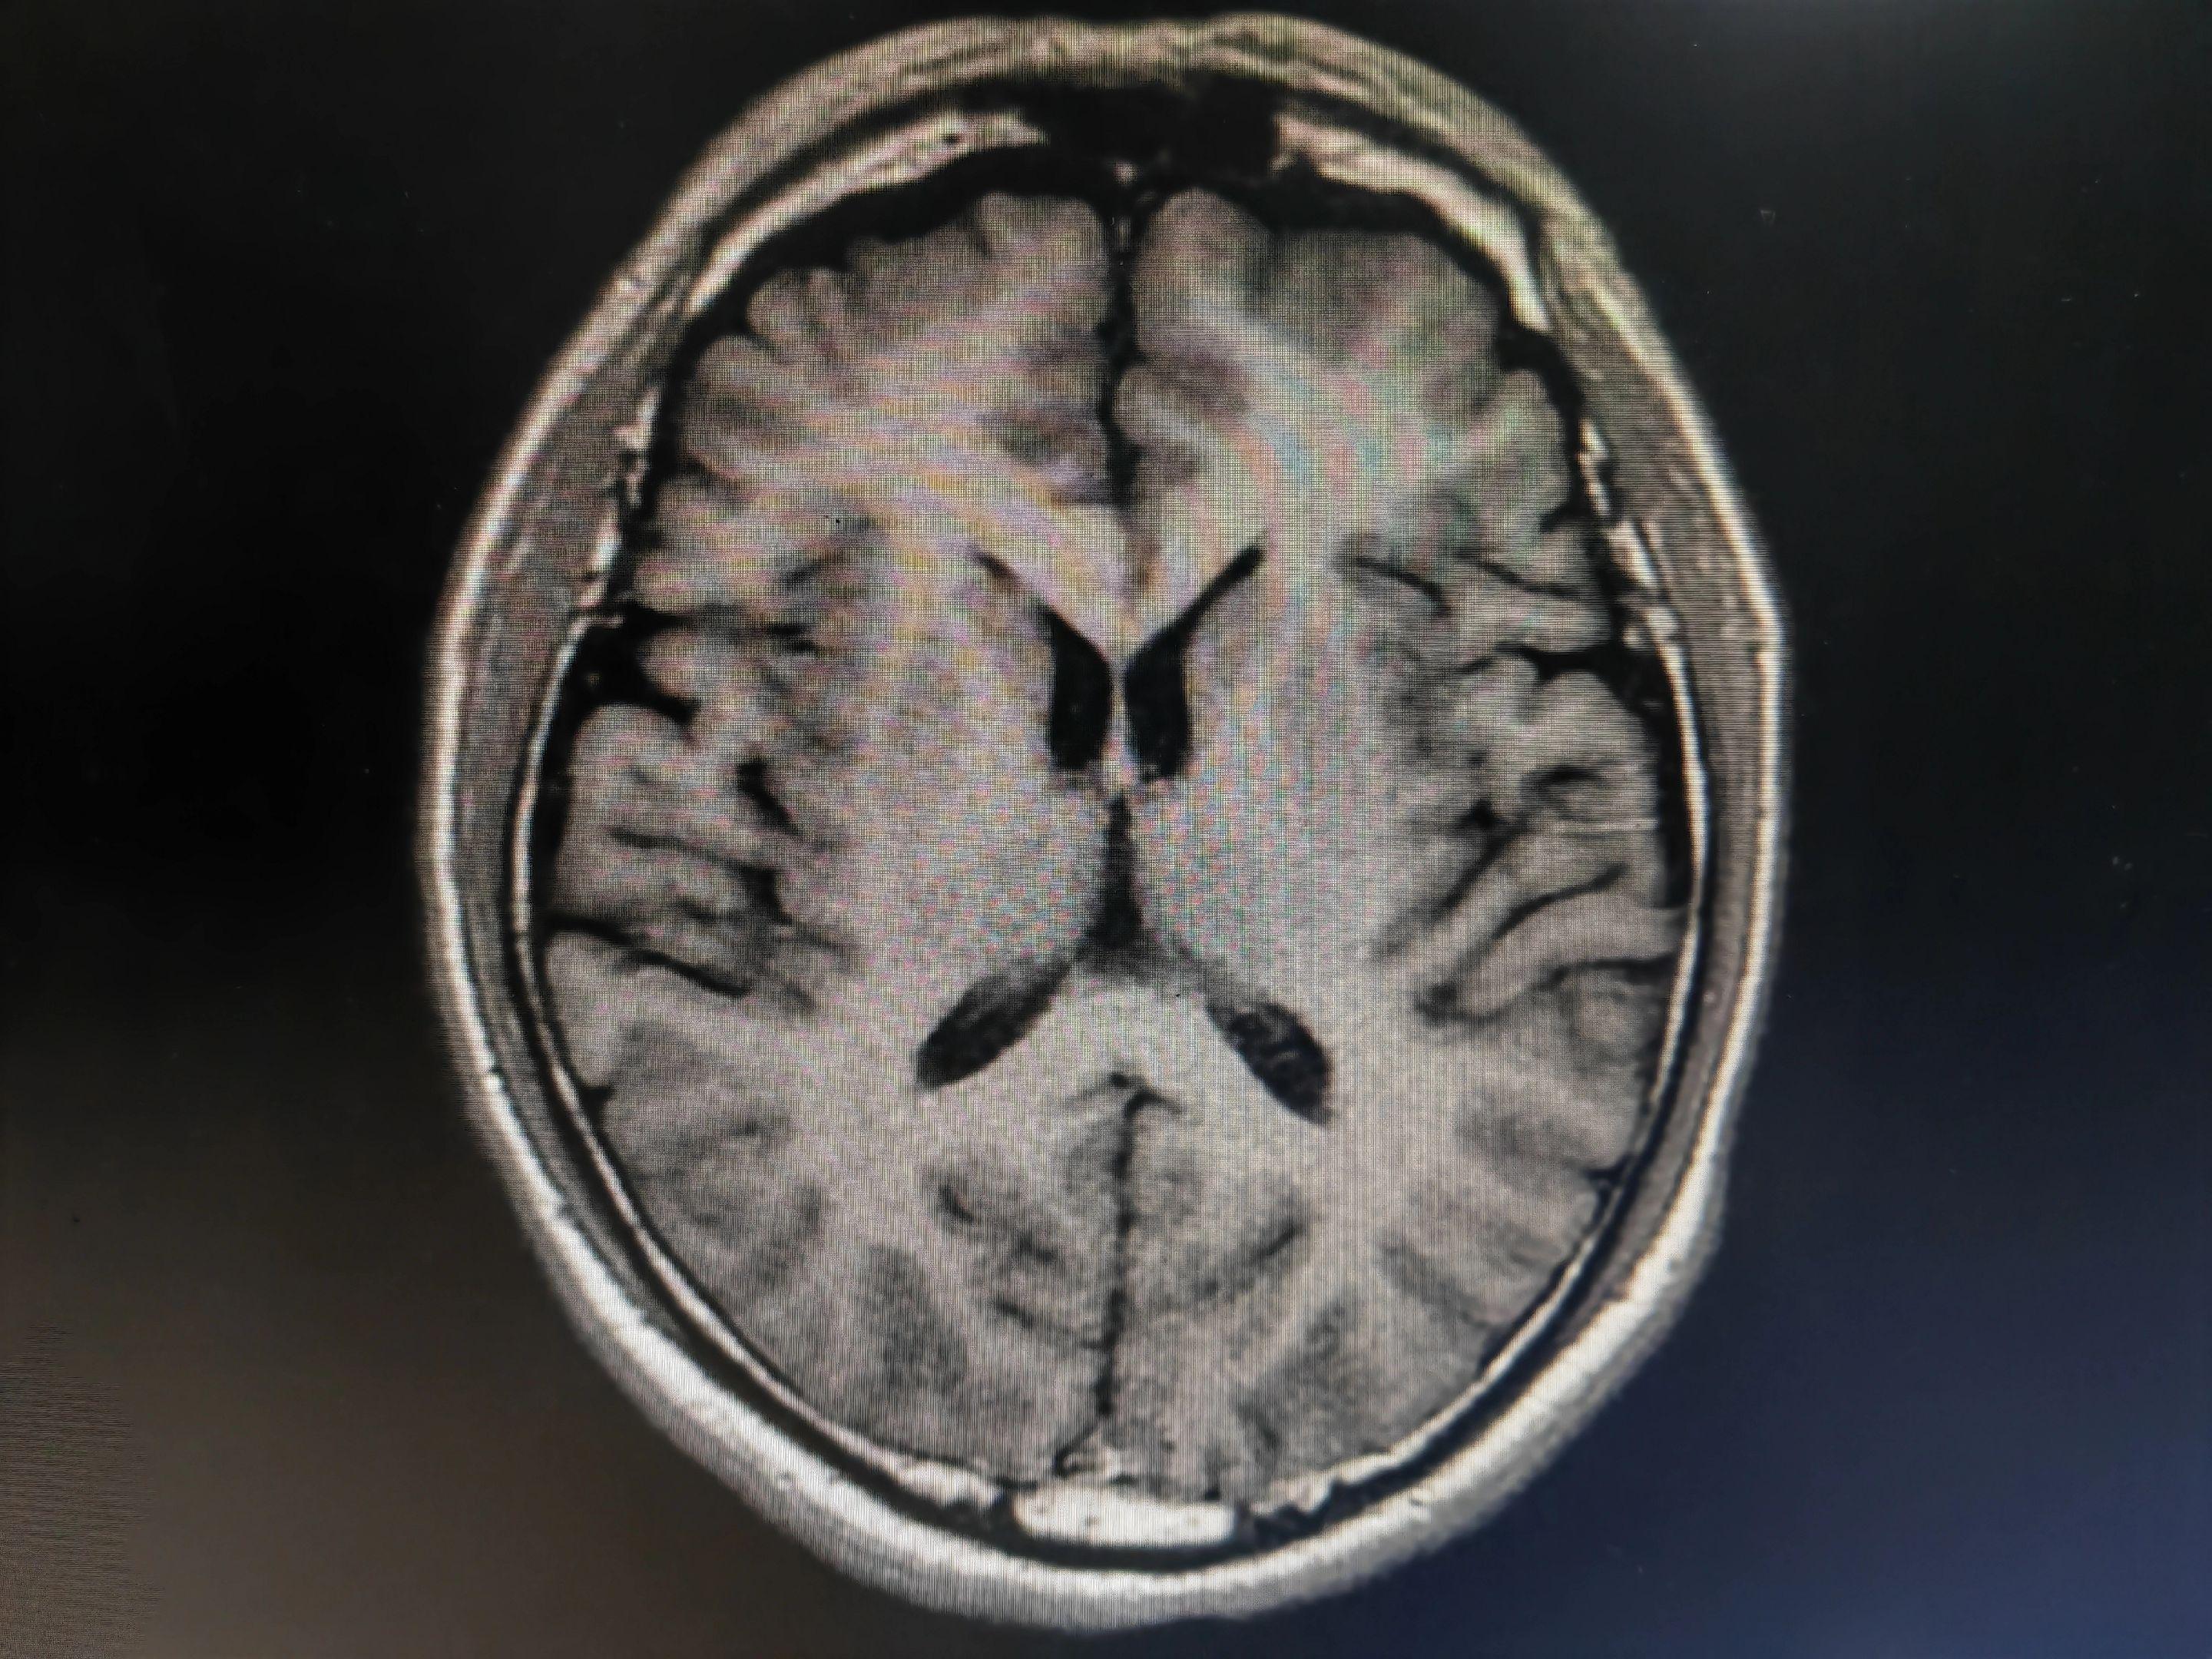

意识模糊伴言语不清的病人 中毒代谢性脑病几种最重要的影像学表现:白色即为受累区域,包括双侧对称性基底节和/或丘脑受累(图A),对称性齿状核受累(图B),皮层灰质受累(图C),对称性脑室周围白质受累(图D),皮质脊髓束受累(图E),胼胝体受累(图F),不对称性白质受累(脱髓鞘疾病;图G),枕顶枕部血管源水肿(图H),脑桥中央受累(I)。